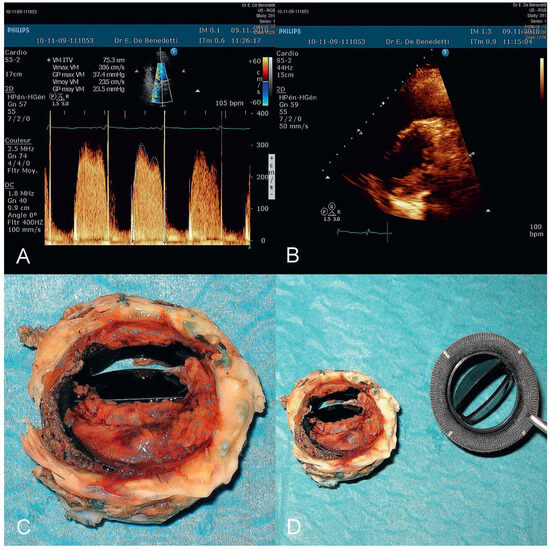

Der 70-jährige Patient wurde uns zugewiesen zur stationären kardialen Rehabilitation bei St. n. mechanischem Aortenklappenersatz wegen schwerer degenerativer Aortenstenose.[...]